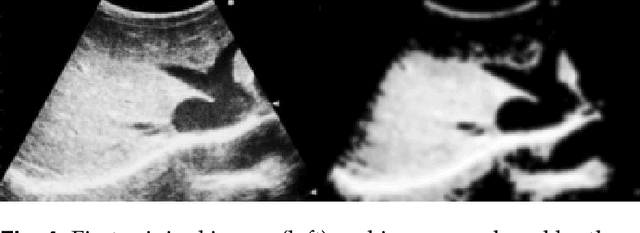

Abstract:Ring Theory states that a ring is an algebraic structure where two binary operations can be performed among the elements addition and multiplication. Binarization is a method of image processing where values within pixels are reduced to a scale from zero to one, with zero representing the most absence of light and one representing the most presence of light. Currently, sonograms are implemented in scanning for congestive heart failure. However, the renowned Playboy Bunny symbol representing the ailment becomes increasingly difficult to isolate due to surrounding organs and lower quality image productions. This paper examines the Otsu thresholding method and incorporates new elements to account for different image features meant to better isolate congestive heart failure indicators in ultrasound images.